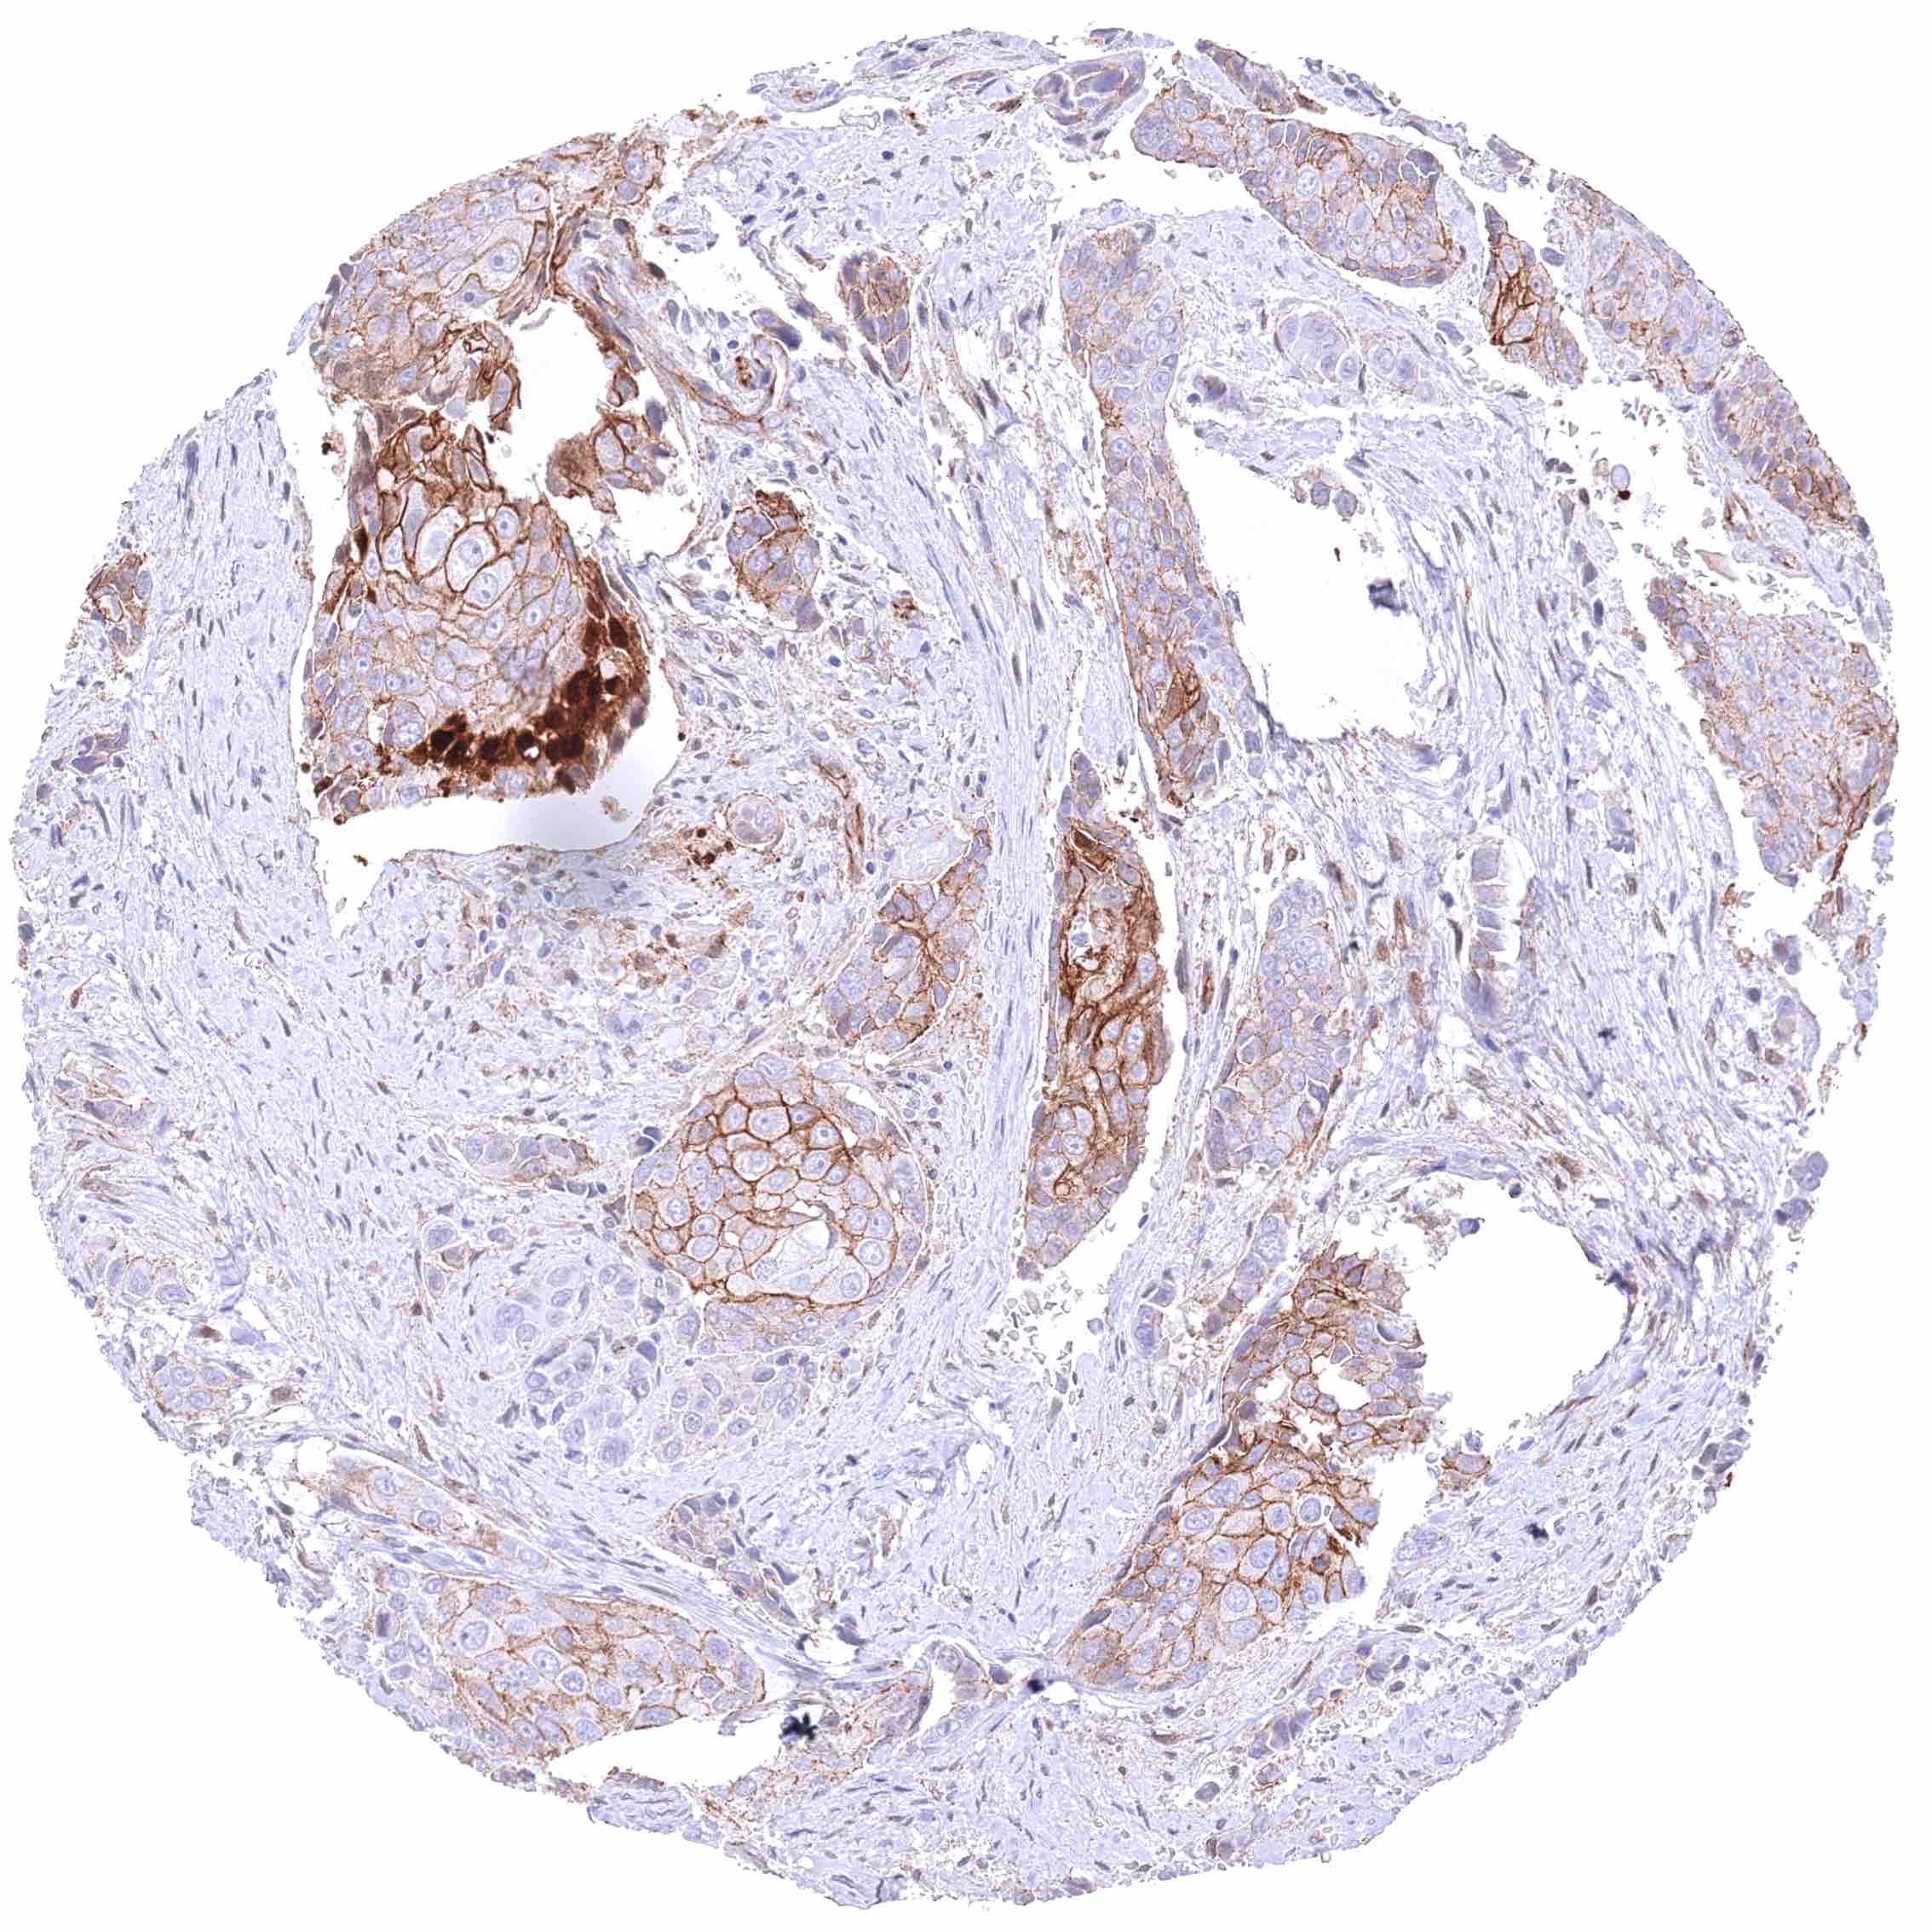

Prostate – Adenocarcinoma (Gleason 3+3=6) with strong membranous β-Catenin staining of tumor cells.